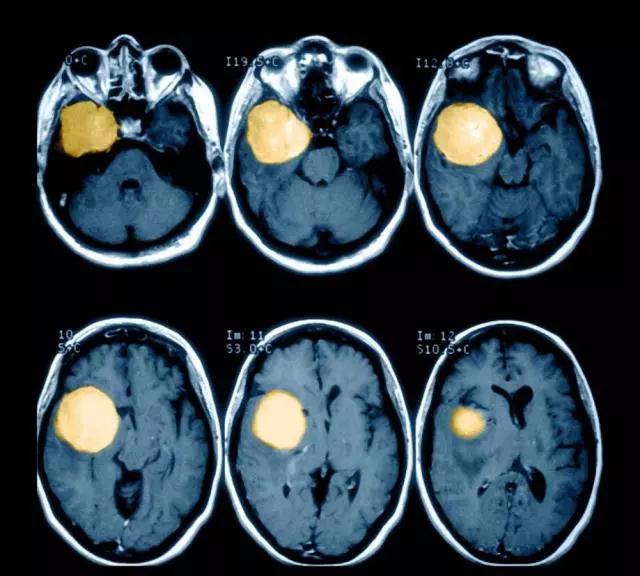

什么是脑肿瘤?

脑肿瘤又称颅内肿瘤,颅脑肿瘤,是指发生于颅腔内的神经系统肿瘤,包括起源于神经上皮、外周神经、脑膜和生殖细胞的肿瘤,淋巴和造血组织肿瘤,蝶鞍区的颅咽管瘤与颗粒细胞瘤,以及转移性肿瘤。

脑肿瘤的分类

1、脑肿瘤按其起源部位可分为原发性颅内肿瘤(起源于颅内组织的肿瘤)和继发性颅内肿瘤(由身体远隔部位转移或由邻近部位延伸至颅内的肿瘤)。

2、按其生物学行为可分为良性颅内肿瘤和恶性颅内肿瘤。